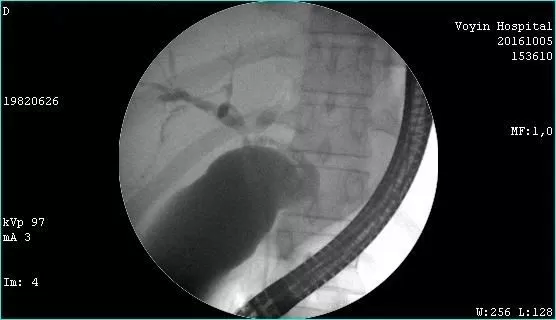

Молодой человек 33 г. Диагноз подтвержден. Стентирован пластиковыми стентами, потом самораскрывающимися. Одномоментно анте и ретроградно - с хорошим результатом. Дальше был поставлен в очередь на трансплантацию. Дальнейшая судьба не известна.